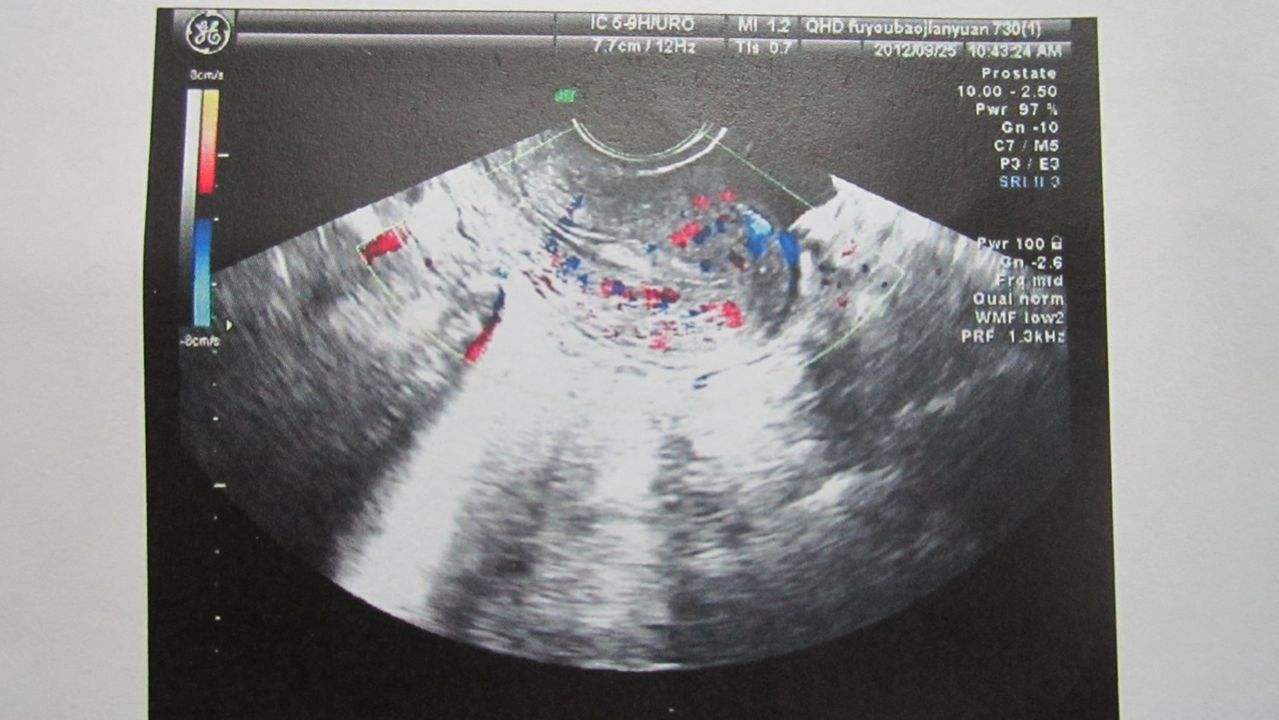

其实阴超与B超都是属于超声检查的一种,只不过B超要憋尿,在体外检查,而阴超,就要把探头放到阴道内做检查。阴超不仅能够检查胎儿,还能检查到女性的子宫,卵巢等生殖器。而且准确率也更高,图像更清晰等。

不过做阴超的时候,女性一般都会特别紧张,毕竟要把探头放进引导内啊,还要在肚子里面看来看去的。不过别担心,医生也会有相应的润滑剂,不会在干涩中导致女性疼痛的。这项检查也非常成熟,一般是在阴道内的4-5厘米地方检查,这个地方是不会对胎儿有什么影响的。

做阴超的话,一般在怀孕初期B超还检测不到胎心胎芽的时候,就能够尝试做阴超了,毕竟阴超比B超早一周能够发现胎心胎压的情况。还能知道孕周哦。再者,如果孕早期出现腹痛或者持续出血的情况,也要做阴超检查一下。毕竟这个时候很可能是流产前兆或者宫外孕。